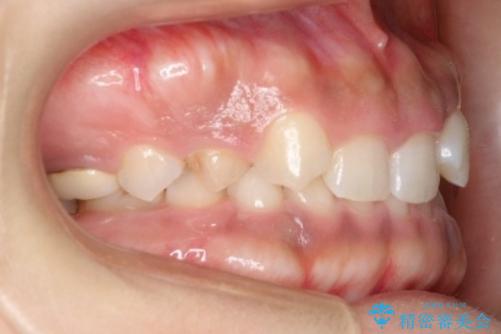

- 後続永久歯が欠損した患者様です。

矯正治療にて歯並びを改善したのち、インプラントにて咬合回復を行う治療計画としました。

捻転が強い部分だけはワイヤーの部分矯正で対応しております。